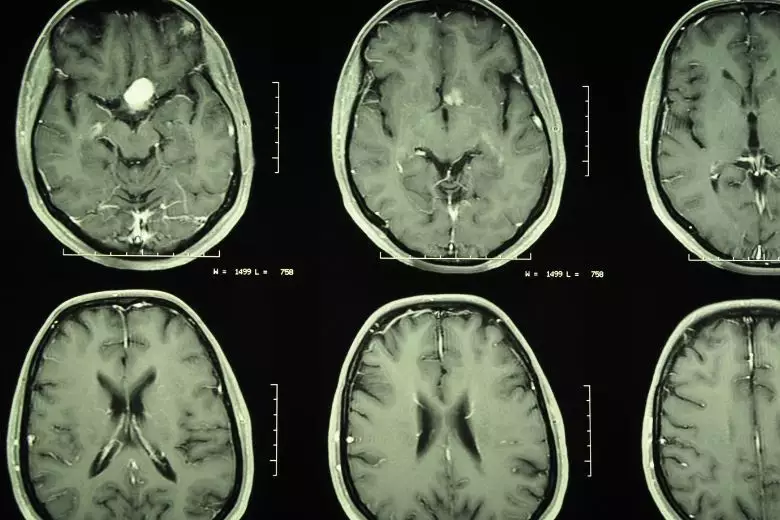

Meningeome sind meist gutartige Hirntumore, die direkt von den Hirnhäuten ausgehen. Sie können prinzipiell an jeder Stelle des Nervensystems auftreten. Die Symptome hängen von der Lage und Größe ab. Die Behandlung erfolgt meist mit einer Operation oder Strahlentherapie.

Je nach Lage im Nervensystem kann das Meningeom durch unterschiedlichste Symptome auffallen. In vielen Fällen auch durch Zufall bei einer Bilduntersuchung aus einem anderen Grund.